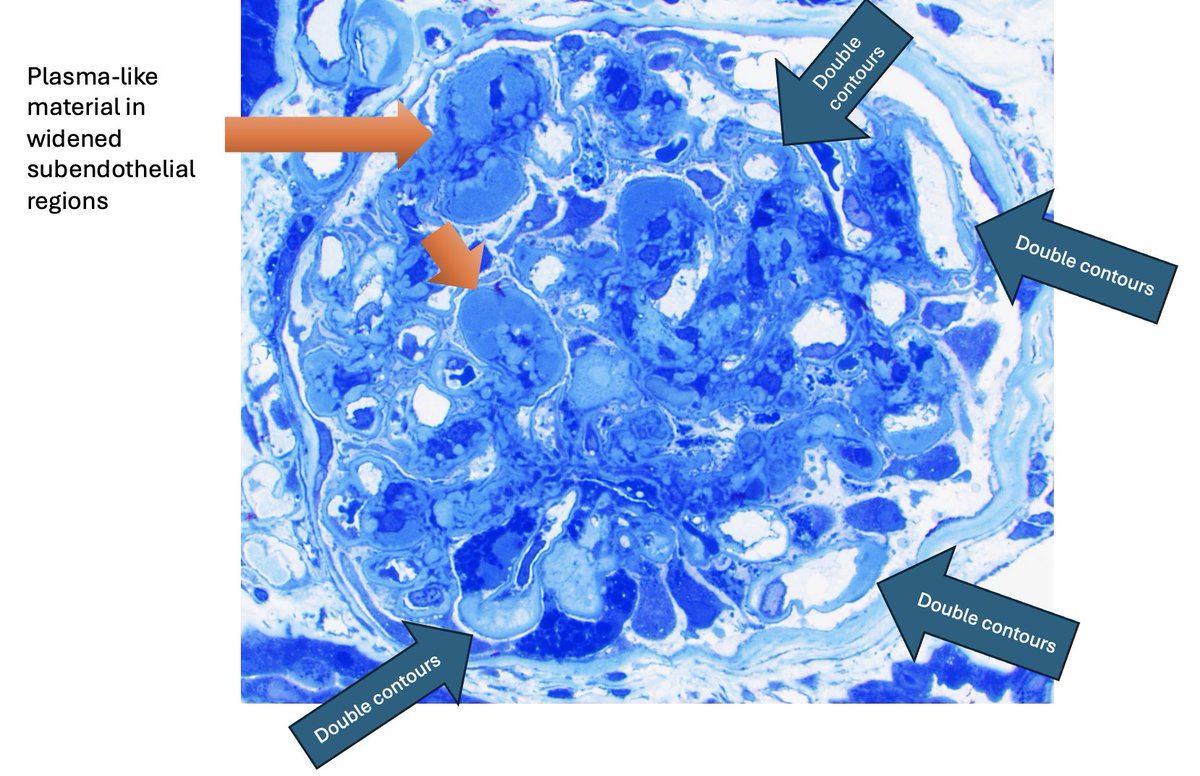

Mini case-series of crystal-storing histiocytosis (CSH) affecting predominantly glomerular loops with detailed literature review of renal CSH, images of one of the cases are depicted below, authors.elsevier.com/c/1Zh4S3uV~y8B…